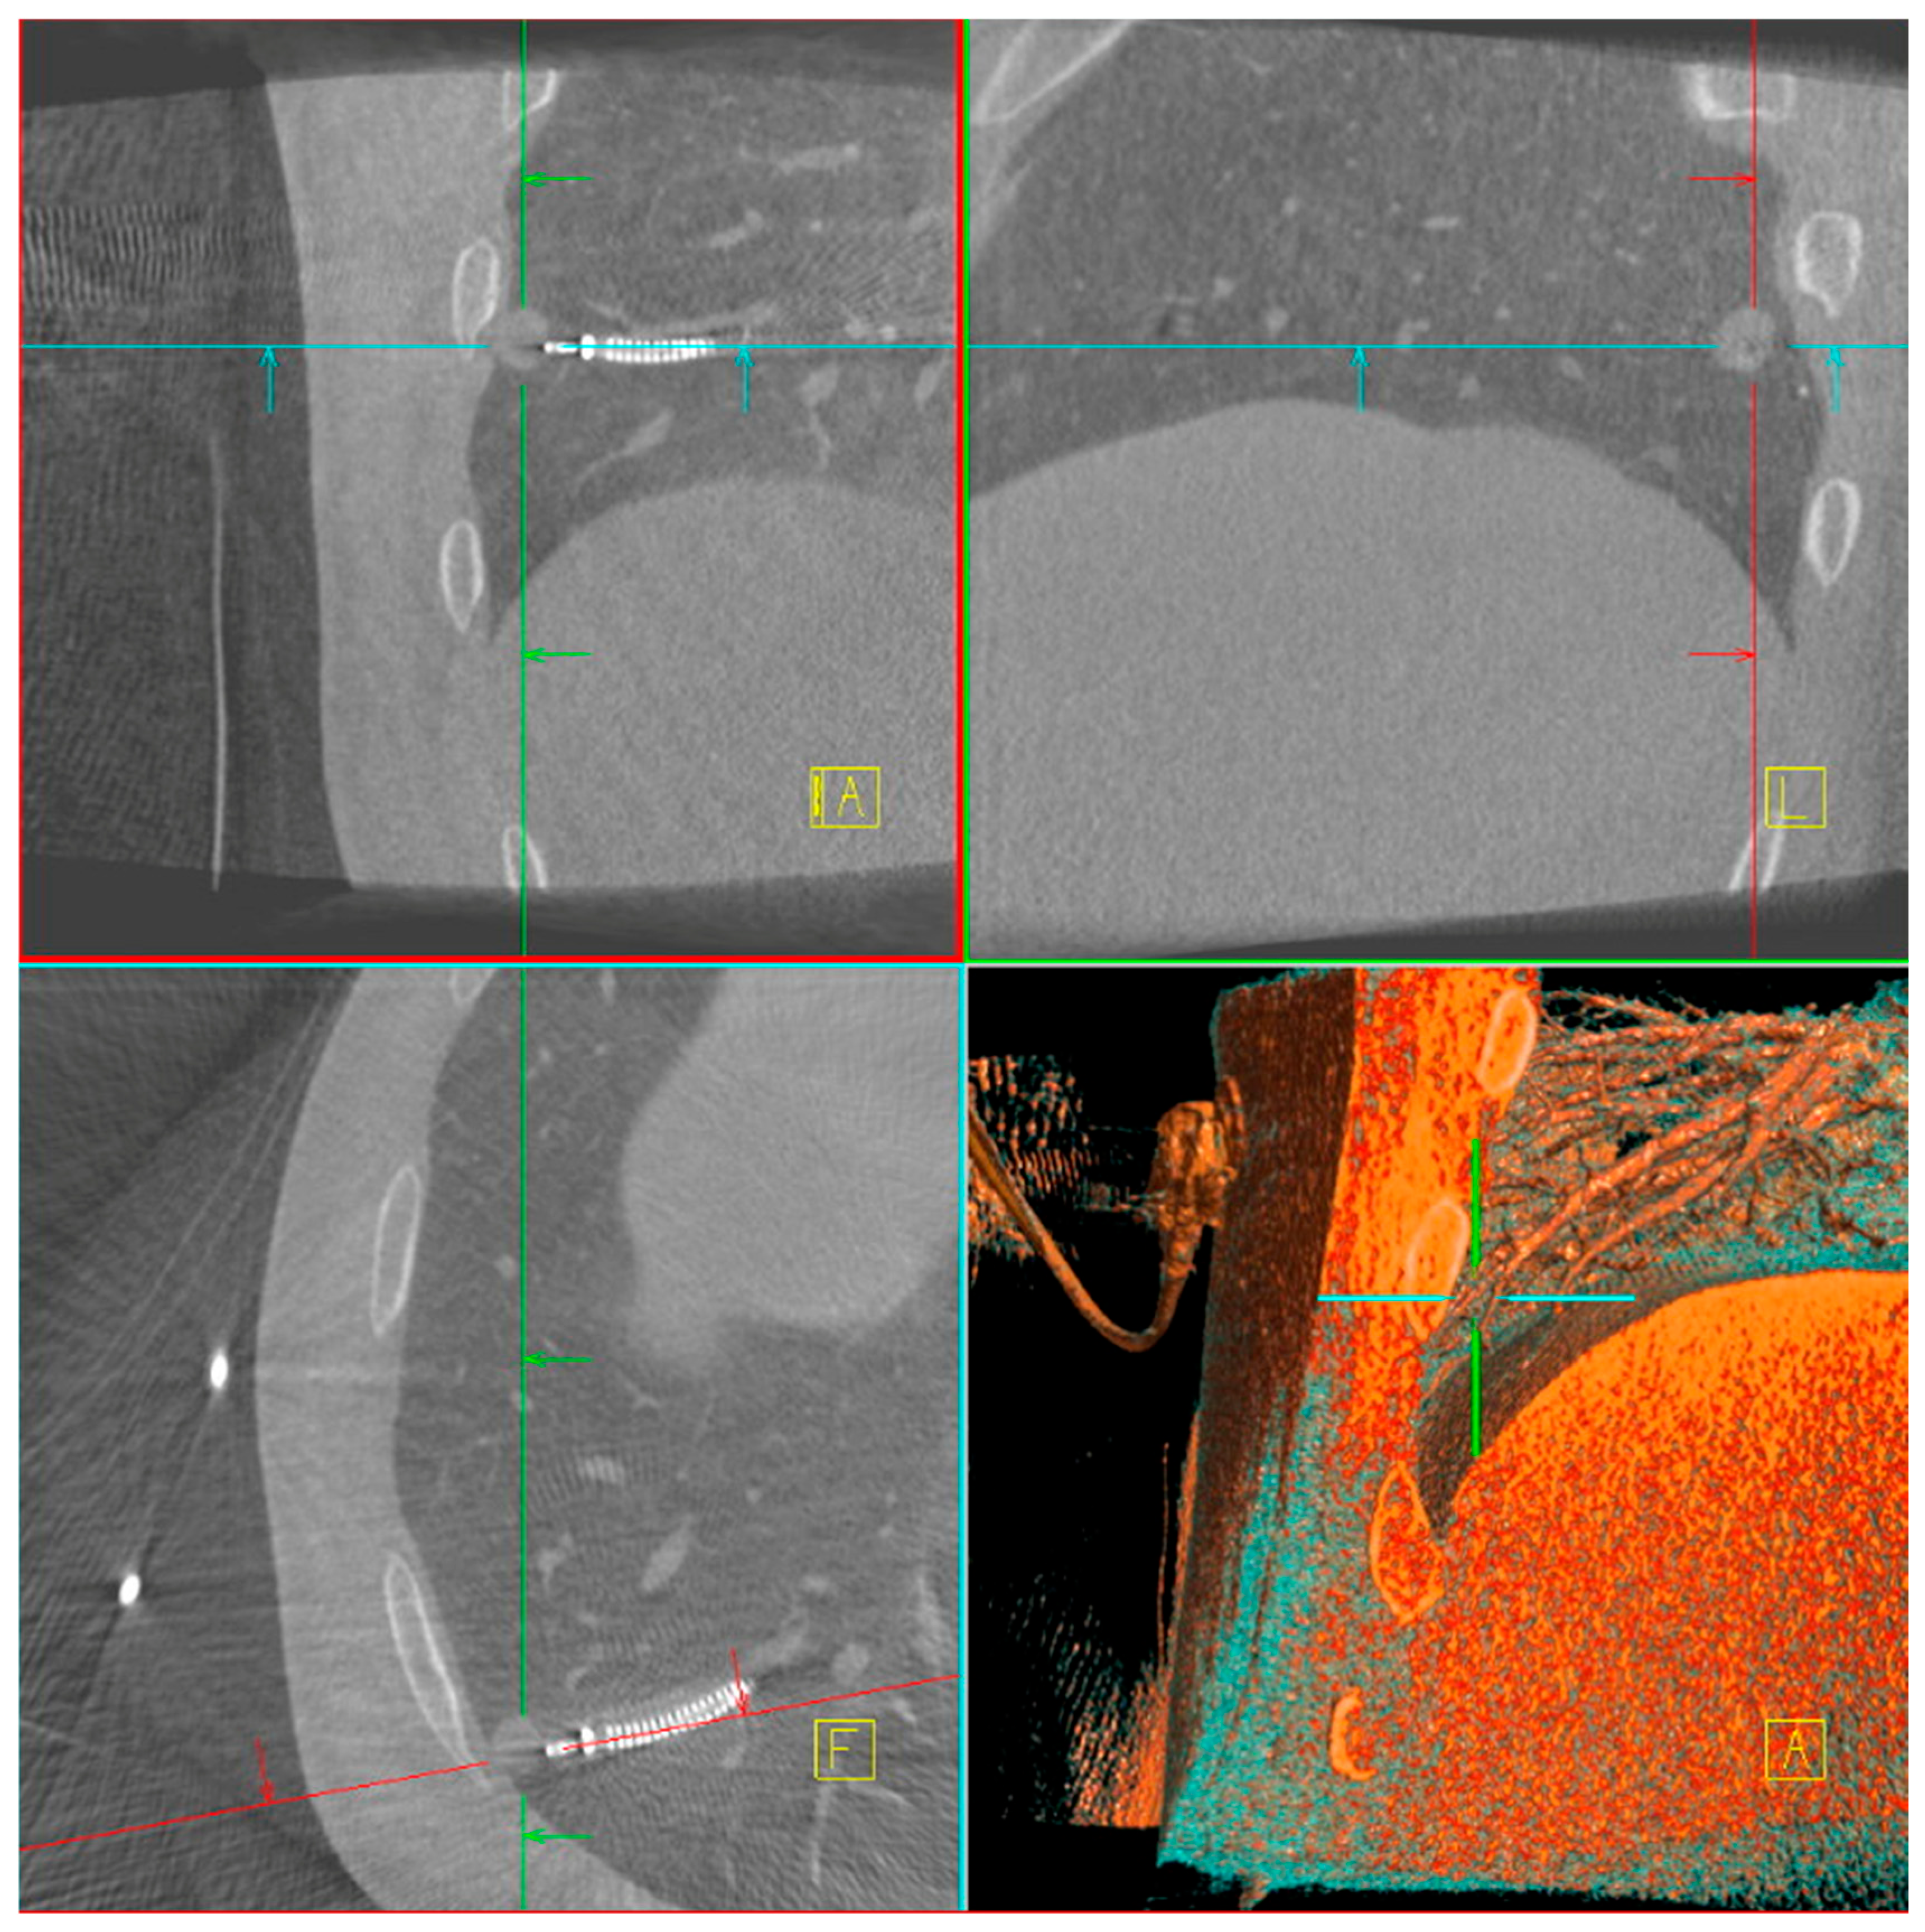

The main difficulty in taking biopsies from a peripheral lung lesion is the target deviation due to different patient positioning on the OR table compared to CT-scan position and forced ventilation during bronchoscopy compared to spontaneous breathing during CT-scan. Several factors contributed to the improved diagnostic yield with CBCT, including target position actualization, tool-in-lesion verification (Figure 1), real-time trajectory adjustment, and enhanced three-dimensional visualization of lesion anatomy. The integration of CBCT and ION is unique in the market as it allows direct transmission of the updated lesion positions to the ION system, enabling precise and dynamic navigation throughout the procedure. [23,24]. While C-arm fluoroscopy remains a more accessible modality, our data emphasize its limitations in achieving the same level of procedural certainty. Similarly, while rEBUS was not used routinely, its selective application in challenging cases contributed to increased confidence in lesion localization, especially in solid nodules with bronchus sign [25,26].

Figure 1. Multiplanar CBCT screenshot taken during robot-assisted bronchoscopy with ION. Coronal, sagittal and axial slices (top left, top right, bottom left) show tool in lesion verification, with the corresponding 3D volume rendering view (bottom right) illustrating the spatial relationship between the bronchoscope trajectory and the lung nodule. Navigation alignment markers are superimposed to confirm positioning.